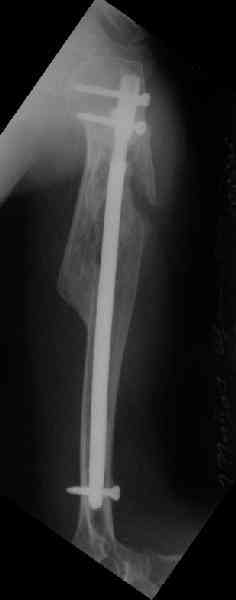

Здесь нет необходимости в серкляже. Вмешиваться на промежуточных отломках приходится, если есть угроза перфорации кожи, или промежуточный отломок попал в фасцию, как пуговица в петлю. В приложении сегментарный оскольчатый перелом плеча в проксимальном отделе, фиксированный больщеберцовым стержнем. Как видите, обошлось без серкляжа. Функция полная.

Это укороченный большеберцовый стержень, которые делает предприятие "ЦИТО".